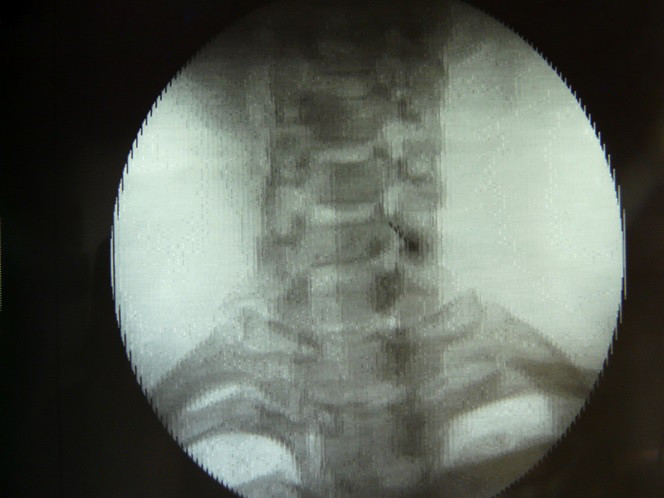

Fig.5. Dosis de anestésico local 5 ml en región de ganglio estrellado izquierdo.

6/6